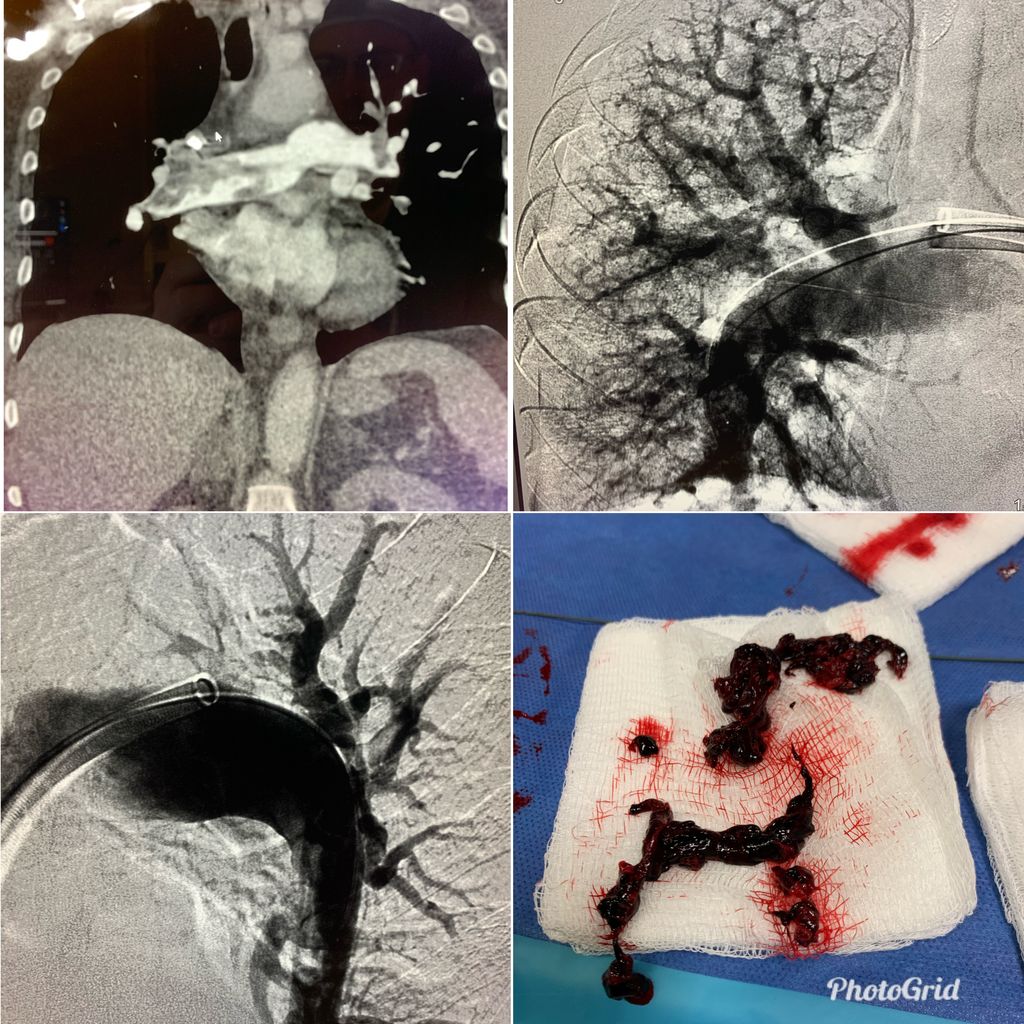

Middle aged patient, COVID + with submassive PE. RV strain, elevated troponin, hypoxia. Treated with T20 flowtriever. 11 passes. PA systolic pressure 67-> 38mmHg. #iRad

It is one of the cases in which the lungs have a large number of #BioClots LMWH such as Enoxaparin breaks part of the clots and there is improvement but high persistent Viral Load generates persistent clots again. Mechanical removal of the numerous pulmonary BioClots is necessary

Aguirre1Gustavo's tweet image. It is one of the cases in which the lungs have a large number of #BioClots

LMWH such as Enoxaparin breaks part of the clots and there is improvement

but high persistent Viral Load generates persistent clots again.

Mechanical removal of the numerous pulmonary BioClots is necessary